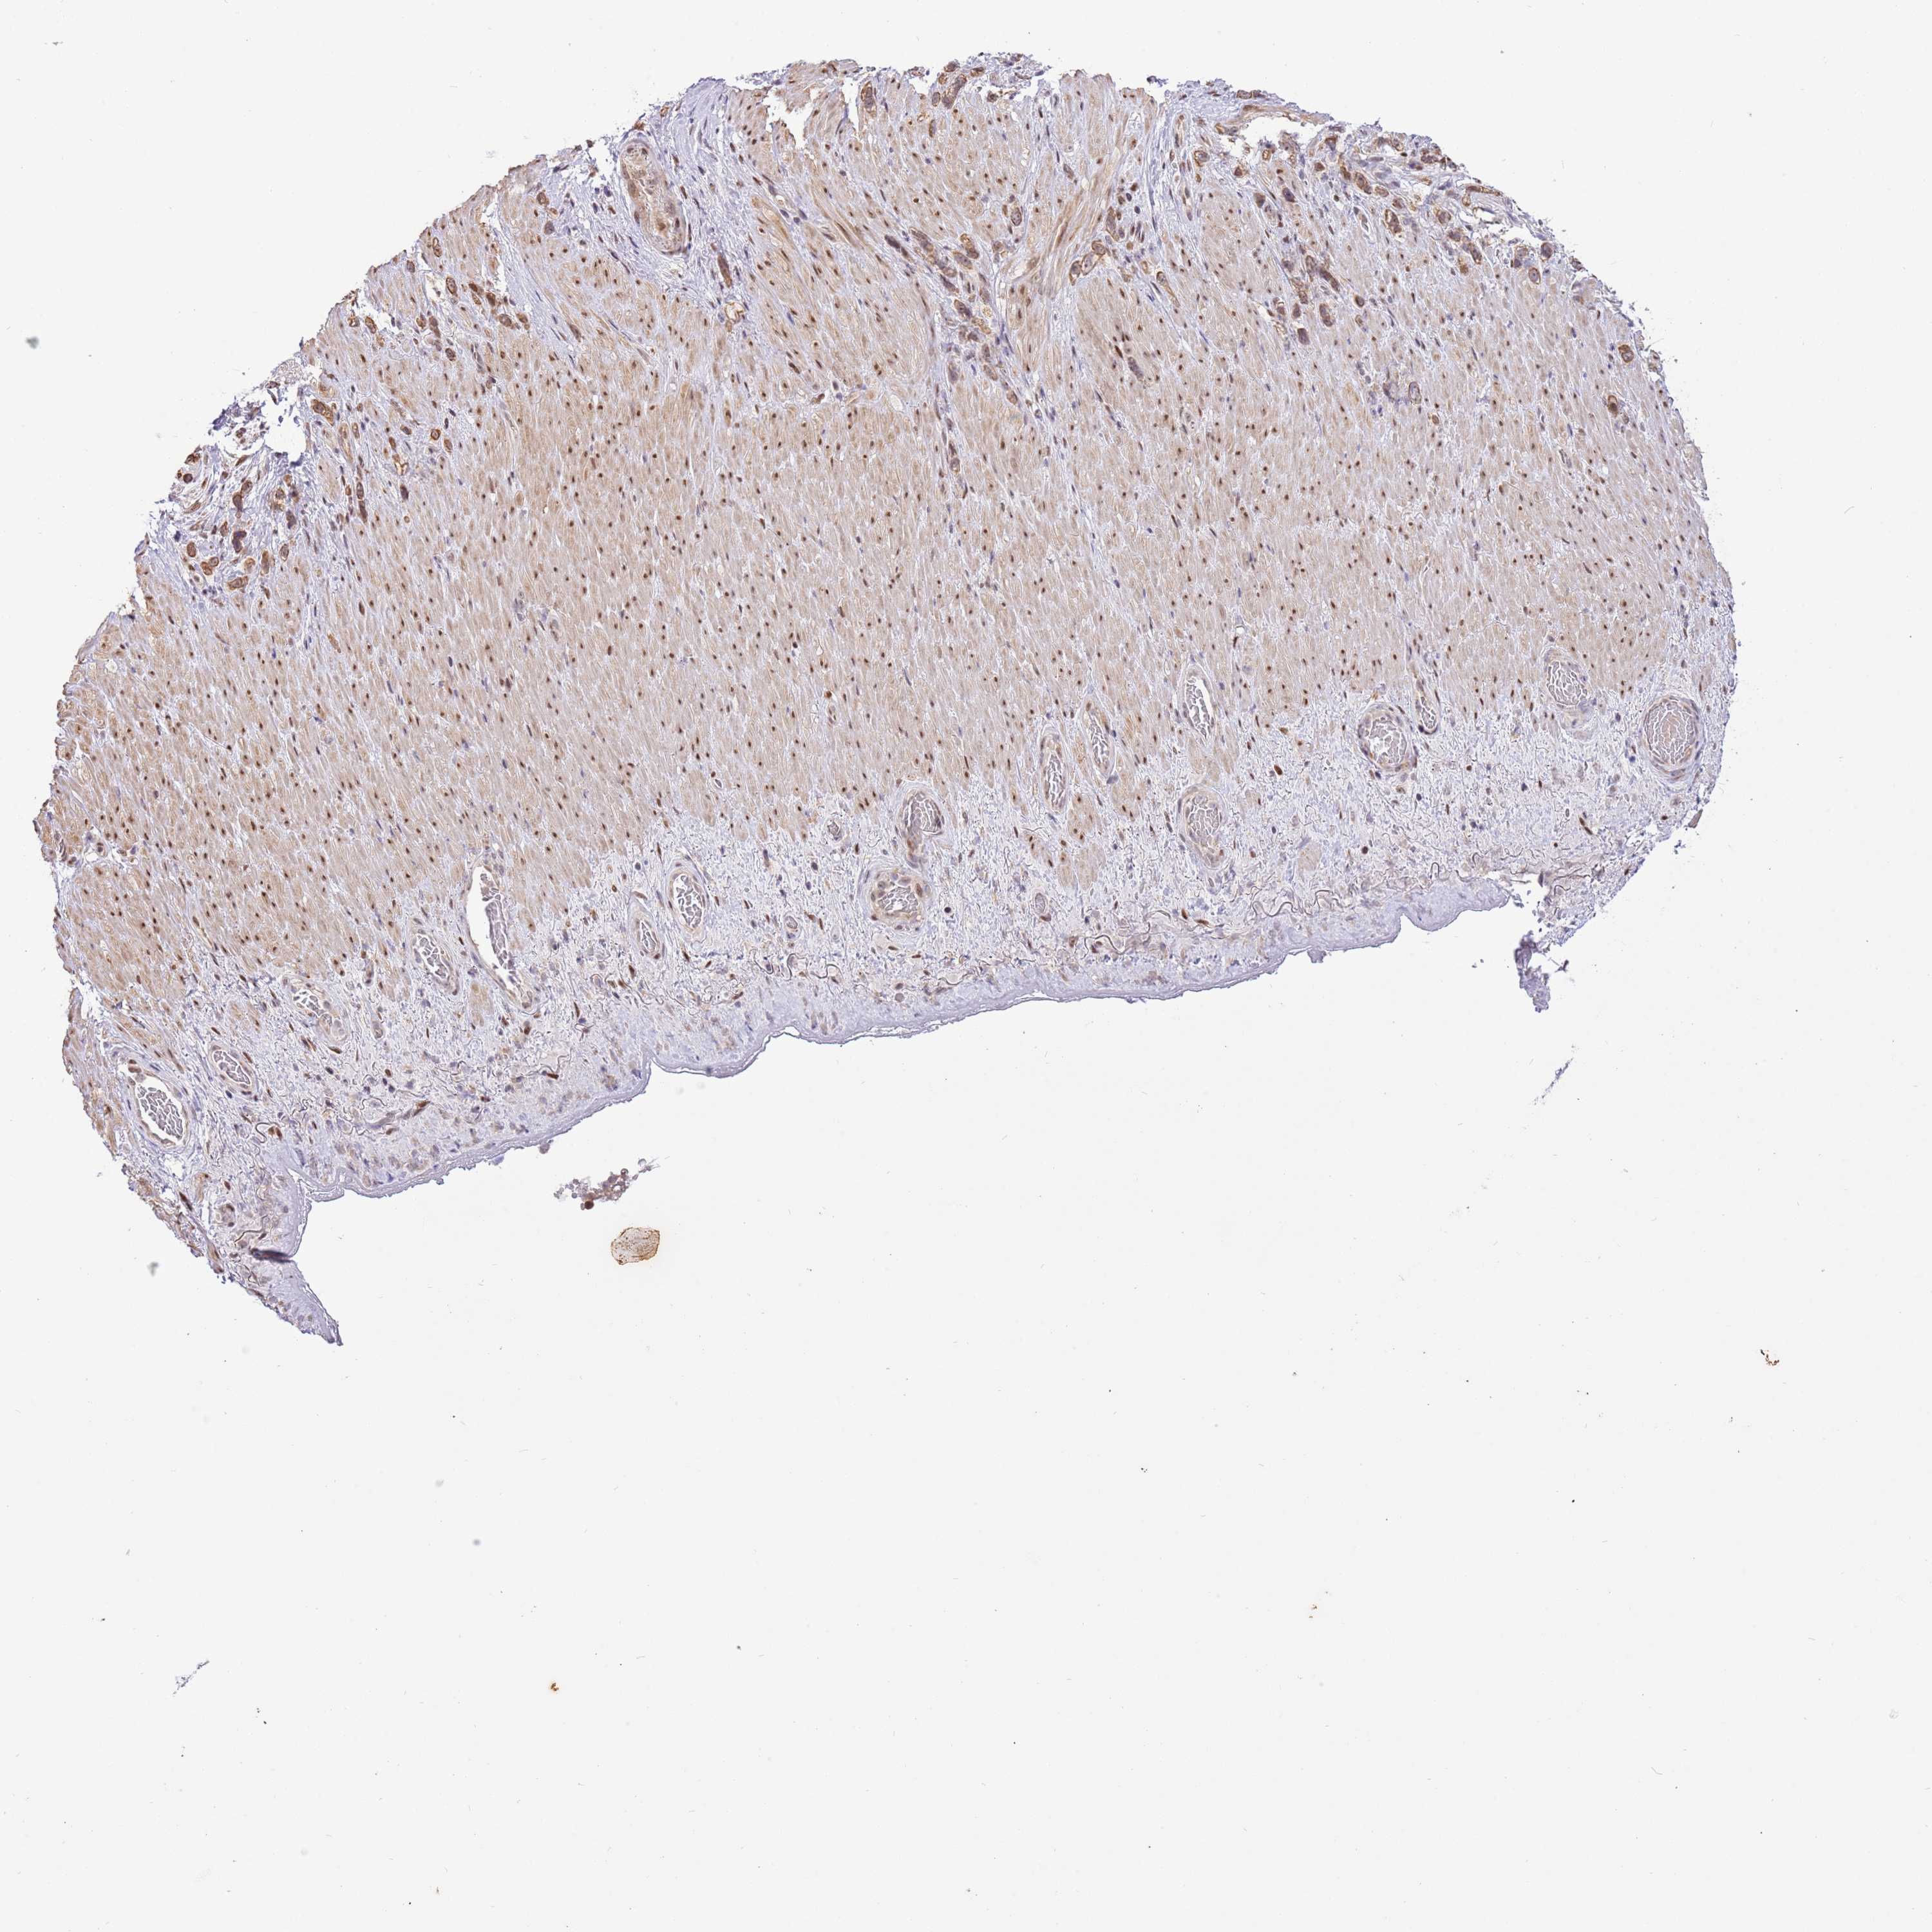

STOMACH CANCER - Protein expressioni

A mouse-over function shows sample information and annotation data. Click on an image to view it in a full screen mode. Samples can be filtered based on level of antibody staining by selecting one or several of the following categories: high, medium, low and not detected. The assay and annotation is described here.

Note that samples used for immunohistochemistry by the Human Protein Atlas do not correspond to samples in the TCGA dataset.

Antibody stainingi

Antibody staining in the annotated cell types in the current human tissue is reported as not detected, low, medium, or high, based on conventional immunohistochemistry profiling in selected tissues. This score is based on the combination of the staining intensity and fraction of stained cells.

Each image is clickable and will lead to virtual microscopy that enables deeper exploration of all samples and also displays staining intensity scores, fraction scores and subcellular localization as well as patient and tissue information for each sample.

Antibody HPA023259

Antibody HPA057163

Antibody CAB033887

Staining

Adenocarcinoma, NOS